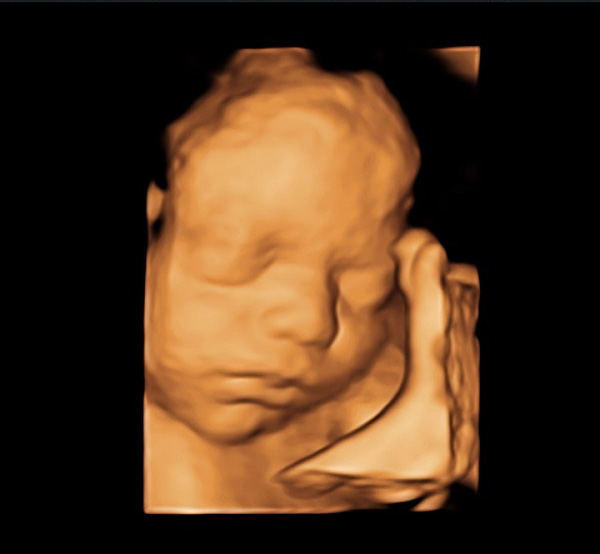

Detaylı ultrason, ikinci düzey ultrason ve ayrıntılı ultrason aynı anlama gelir. Renkli ultrason veya 4 boyutlu ultrason detaylı ultrasonla aynı şey değildir. 4 boyutlu ultrasonda bebeğinizin yüzü veya organlarının güzel bir anı olarak saklanacak fotoğrafı alınır. Detaylı ultrasonda ise bebeğin bütün organları ultrason teknolojisi el verdiğince incelenir

Detaylı ultrasonun yapıldığı cihazın görüntü kalitesi çok iyi olmalıdır. Ayrıca detaylı ultrason için kullanılan cihazın doppler özelliğinin olması gerekir. Yüz gibi bazı kısımlar iki boyutlu ultrasondan ziyade dört boyutlu ultrasonla daha iyi değerlendirilir.